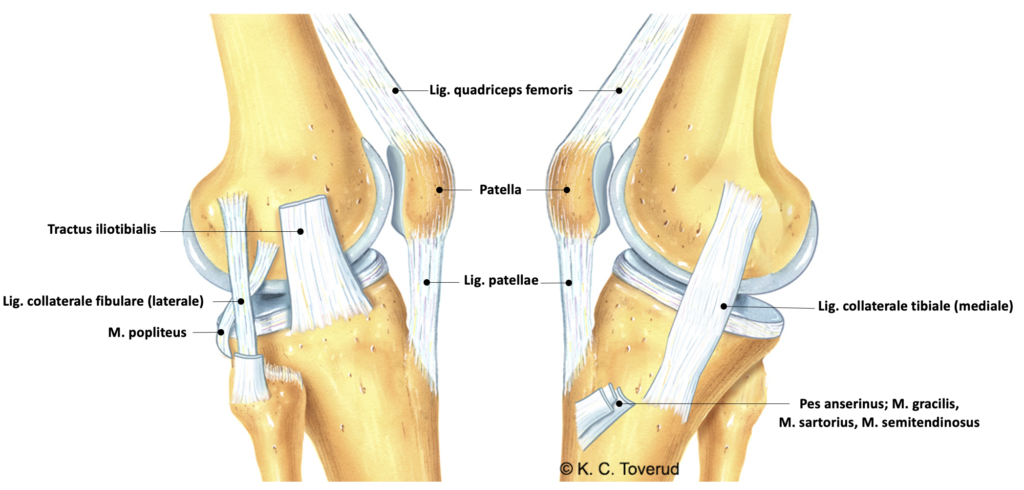

Sideligamenter: Testes først med strakt kne og deretter med kneet 20° flektert. Med strakt kne sidestabiliseres kneleddet av ligamentene i bakre kapsel, bakre og fremre korsbånd og m poplitus. Når kneleddet flekteres til 20° blir collateralligamentene primære stabilisatorer alene og valgusstress (adduksjon) tester nå ligamentum collaterale mediale og varusstress (abduksjon) tester ligamentum collaterale laterale.

Varus med strakt kne, Ligamentum collaterale laterale. Smerter.

Varus med 30° flektert kne, Ligamentum collaterale laterale. Instabilitet.

Valgus med strakt kne, Ligamentum collaterale mediale. Smerter.

Valgus med 30° flektert kne, Ligamentum collaterale mediale. Instabilitet.

Kne, ligamenter og muskelfester

Valgusinstabilitet

- Primær stabilisator

- Lig. collaterale mediale

- Sekundære stabilisatorer

- Bakre mediale kapsel

- m. semimebranosus

- Fremre og bakre korsbånd

- Pes anserinus (m sarorius, m gracilis, m semitendinosus)

- m. gastrocnemius mediale hode

- Kompresjon av laterale menisk

Varusinstabilitet

- Lig. collaterale laterale

- Bakre laterale kapsel

- m. popliteus

- Traktus iliotibialis

- m. gastrocnemius laterale hode

- Kompresjon av mediale menisk